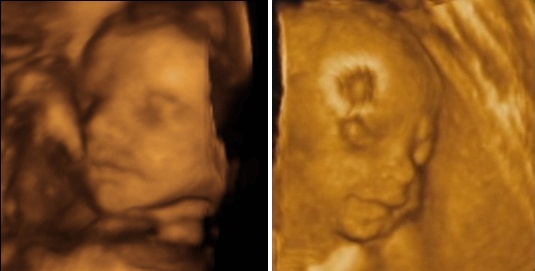

Testvérek [/img]